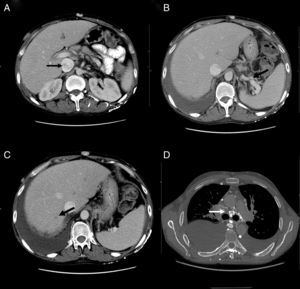

Durante su ingreso, se constató aumento de los edemas de miembros inferiores, al que se le añade edema escrotal y de pared abdominal. Se inició tratamiento diurético con parcial mejoría. En la analítica de ingreso (tabla 1) destacaba la persistencia de leucocitosis, elevación de reactantes de fase aguda, hipoproteinemia e hipoalbuminemia, función hepática y renal normal. El estudio de autoinmunidad (anticuerpos antinucleares, anticuerpos extraíbles del núcleo, anticuerpos anticitoplasmáticos, factor reumatoide, anticuerpos anti citrulinas), los hemocultivos, la serología viral para hepatitis B y C y virus de inmunodeficiencia humana fueron negativos. Se practicó un ecocardiograma que mostró un mínimo derrame pericárdico, sin signos sugestivos de constricción. Una ecografía Doppler de abdomen constató la presencia de hepatomegalia homogénea y ascitis leve. Las venas suprahepáticas media e izquierda sin presencia de flujo (síndrome de Budd-Chiari). La vena suprahepática derecha estaba parcialmente permeable con flujo monofásico y la vena cava inferior presentaba un ligero aumento de calibre. Se evidenciaron además signos de hipertensión portal con circulación colateral en el hilio esplénico, retroperitoneal y repermeabilización de la vena umbilical. Estos hallazgos se corroboraron en una tomografía abdominal (fig. 2A-C). En el estudio de orina, se observó una proteinuria de 0,1g/24 h. Dada la presencia de hipoproteinemia, hipoalbuminemia y déficit vitamínico, se sospechó de un síndrome malabsortivo. El estudio de transglutaminasa sérica también resultó normal. Se practicó una biopsia de grasa abdominal subcutánea, en donde no se evidenció material amiloide. La colonoscopia y la ileoscopia descartaron la presencia de ileítis. Debido a la hipertensión venosa portal, esplácnica y enteropatía pierdeproteína, se sospechó de linfangiectasia intestinal que se confirmó con la elevada excreción elevada de alfa 1 antitripsina fecal (2,85mg/g-valor normal < 0,3) e imágenes compatibles halladas con cápsula endoscópica en el tracto duodenal (fig. 1D). Durante su estancia, el paciente cursó con episodios recurrentes de tromboflebitis, por lo que precisó de la colocación de una vía central (femoral) que se trombosó a las 72 h. Ante la imposibilidad de administración de tratamiento por vía intravenosa, se colocó una vía central con ayuda de arteriografía con evidencia de gran circulación colateral en el tórax y supraclavicular (fig. 2D). La yugular interna se encontraba disminuida de calibre y la yugular externa dilatada, a la inyección de contraste se apreciaba una trombosis de ambos troncos innominados con abundante circulación colateral que drenaban a la vena pericardiofrénica. Se logró cateterizar dicha vena, donde se colocó un reservorio subcutáneo bicameral que el paciente toleró únicamente 24 h por dolor en el momento de la administración de la medicación.

A) Tomografía computarizada, corte axial: muestra heterogenicidad de la vena cava inferior. B) Tomografía computarizada, corte axial: muestra circulación colateral en el hilo esplénico. C) Tomografía computarizada, corte axial: muestra defecto de repleción suprahepática. D) Angiotomografía, corte axial: muestra circulación colateral mediastínica.